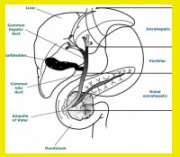

| 11:17, 27 במאי 2013 | Gallbladder14.jpg (קובץ) |  |

36 קילו־בייטים | Zvi kaufman | 2 | |

| 11:15, 27 במאי 2013 | Gallbladder6.jpg (קובץ) |  |

56 קילו־בייטים | Zvi kaufman | 2 | |

| 11:10, 27 במאי 2013 | Gallbladder5.jpg (קובץ) |  |

61 קילו־בייטים | Zvi kaufman | 4 | |

| 11:02, 27 במאי 2013 | Gallbladder4.jpg (קובץ) |  |

33 קילו־בייטים | Zvi kaufman | 2 | |

| 11:00, 27 במאי 2013 | Gallbladder3.jpg (קובץ) |  |

62 קילו־בייטים | Zvi kaufman | 2 | |

| 10:59, 27 במאי 2013 | Gallbladder2.jpg (קובץ) |  |

176 קילו־בייטים | Zvi kaufman | 2 | |

| 10:57, 27 במאי 2013 | Gallbladder1.jpg (קובץ) |  |

43 קילו־בייטים | Zvi kaufman | 2 | |

| 04:13, 23 במאי 2013 | Gallbladder13.jpg (קובץ) |  |

29 קילו־בייטים | Zvi kaufman | שוחזר לגרסה מ־04:11, 23 במאי 2013 | 5 |